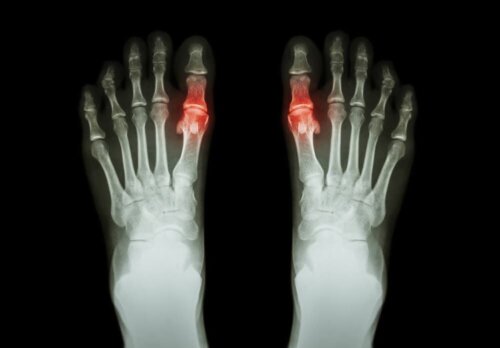

Artritis heeft de neiging om te verschijnen in de vorm van pijn en moeite met het bewegen van de aangetaste gewricht of gewrichten. Soms gaat het ook om stijfheid en zwelling in hetzelfde gebied. Het kan invloed hebben op slechts één gewricht of veel gewrichten op hetzelfde moment. Het kan ook symmetrisch of asymmetrisch zijn.

Elk type heeft zijn deeltjes, en de tijd die de symptomen kunnen duren is variabel. Bijvoorbeeld, reumatoïde artritis is een symmetrisch type van artritis dat invloed heeft op kleine gewrichten, zoals die van de vingers. Jicht, aan de andere kant, is een type van artritis die de neiging om slechts een gewricht te beïnvloeden.